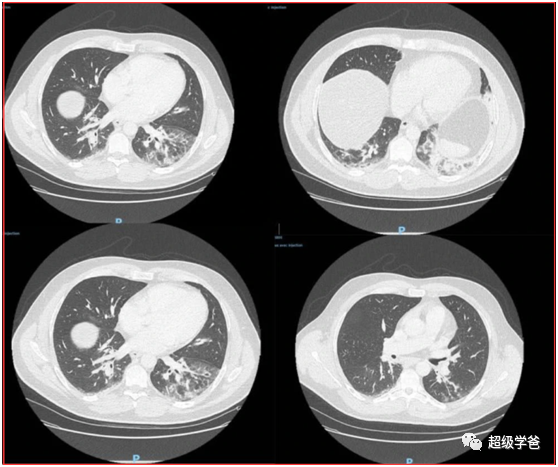

他们筛选的依据是:发烧高于38.5度,咳嗽、鼻炎、喉咙痛或肌肉酸痛和CT毛玻璃样混浊的。这都是新冠肺炎的典型症状。

所幸的是,14名患者的医学采集标本都进行了保留,于是他们进行了核酸检测,结果有了惊人的发现,其中一名患者是阳性,但当时是被当作流感治疗的。

这名患者是一名鱼贩子,长期生活在法国,最后一次旅行是在2019年8月去过阿尔及利亚,没有武汉旅行史和接触史。

他是2019年12月27日被送进急救室的,表现为咯血,咳嗽,头痛和发烧,已经持续了4天。CT检查肺部呈现毛玻璃不透明,典型的新冠肺炎症状。

考虑到他已经出现症状4天,加上潜伏期,至少可以把法国的疫情倒推至12月中旬。而他一个孩子在他住院之前也出现了类似的症状,也按照流感治的。

由于他没有明确的感染途径,所以这说明法国在12月中旬就存在社区传染了,也就意味着法国在12月初甚至11月就出现了新冠疫情。